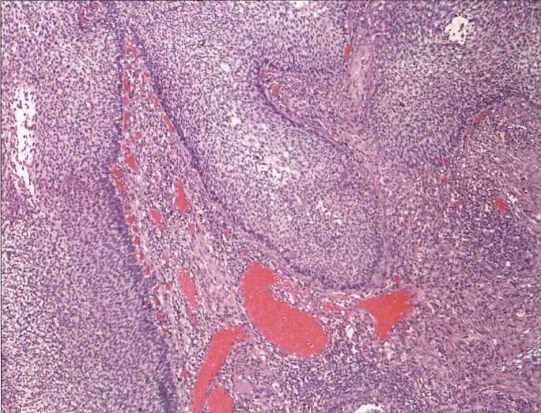

7.淋巴上皮瘤样癌:细胞大小一致,核空泡状,可见核分,胞质淡染,散在/成簇分布在丰富的淋巴组织中,与EBV感染无关。